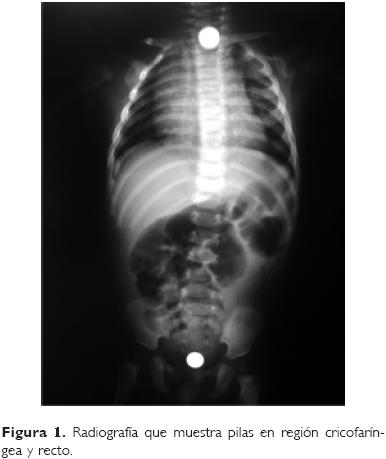

La pila se localizó en el tercio superior del esófago en 17 pacientes, en tercio medio en dos y en tercio inferior en uno; en un caso no se encontró la pila al momento de la endoscopia, pero se observó lesión del tercio superior del esófago. En un paciente se encontró una batería en el tercio superior del esófago y una segunda pila en ámpula rectal (Fig. 1).

El estrecho cricofaríngeo es el sitio más común de obstrucción, con 60 a 70%, seguido por el esófago medio, 10 a 20%, y el inferior con 20%;2 en el estudio que aquí se presenta encontramos una frecuencia mayor en el esófago superior con 81%, observándose en tercio medio de 11.2% y en el inferior con 4.7%. En el lactante de tres meses de edad se encontraron dos pilas, una a nivel del cricofaríngeo y la otra en recto.